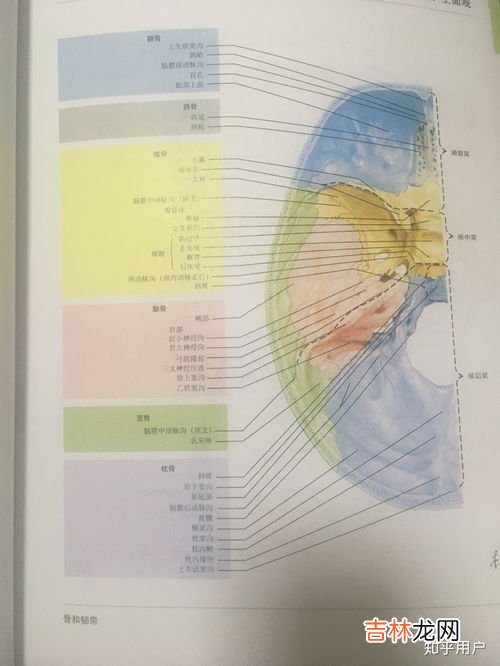

3、人的头部哪里最脆弱太阳穴是颅骨骨板最薄弱的部位 。

太阳穴的位置是颅顶骨、额骨、蝶骨及颞骨的交汇之处,称为“翼点”或“翼缝” 。此处是颅骨骨板最薄 , 而且是骨质脆弱的部位 。颅骨为一层坚硬的骨板,对脑起着保护作用 。颅骨骨板各处薄厚不一,平均厚度为5毫米 , 最厚处为1厘米 。而太阳穴处的骨板厚度仅为1——2毫米,是颅骨最薄弱的部份,受到暴力打击,很容易形成骨折 。骨折后可直接影响脑的功能 。

太阳穴遭暴力打击 , 不仅可以因颅骨颞鳞部骨折损伤脑膜中动脉,而且常常可以在颅骨完整的情况下损伤脑膜中动、静脉,在中颅窝基底部形成硬膜外血肿 。脑膜中动脉破裂形成血肿 , 不仅十分迅速,而且后果极为严重 。

脑膜中动脉破裂,可使人立即陷入昏迷,昏迷后的间歇清醒期极短,多则不足1小时 , 少则只有10分钟 , 常常在损伤两小时后完全昏迷 。如果伤后6小时仍不能有效地制止出血,即可以致命 。